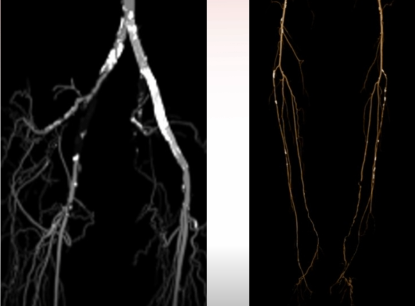

ROS分期Ⅲ级,ABI 0.3;

CT提示右侧髂总动脉闭塞合并股总动脉重度狭窄。

左侧病变已处理,右侧因复杂未处理。

图:术前CT